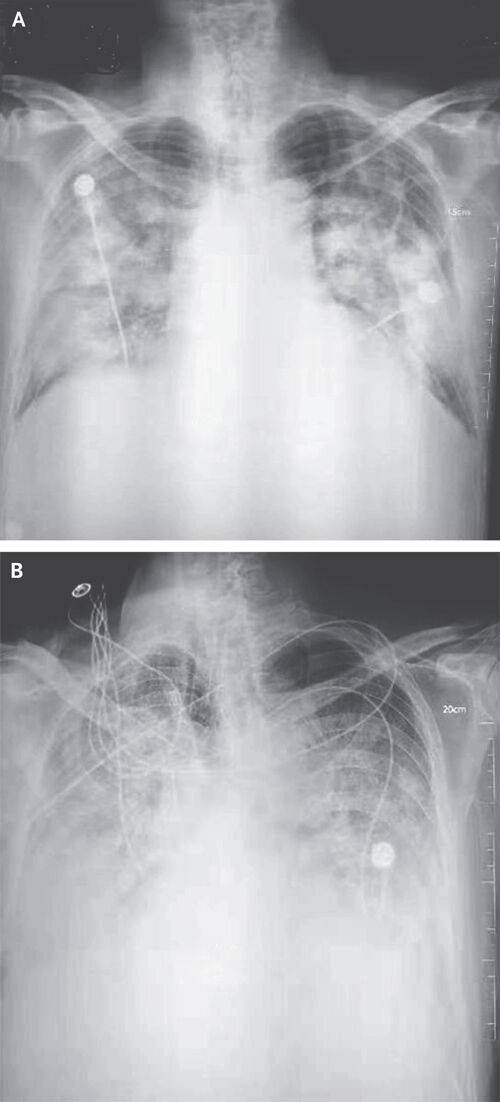

▲ 우한 폐렴 환자의 흉부 방사선 사진

(사진=NEJM 논문 발췌, 연합뉴스)